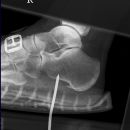

Birkenstockrefixation